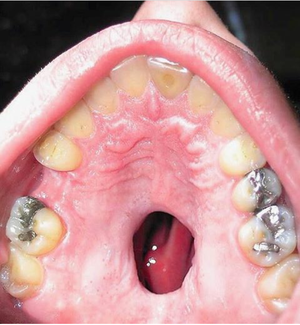

A side effect of cocaine use!

Palatal tumor may be kapposi sarcom . I don't know but I'm sure it need to take first biopsy and then will see it